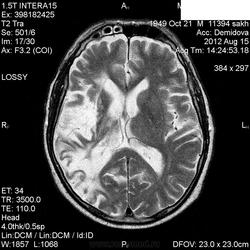

1 случай -локальная гемиатрофия.2 случай-диффузная.

Молодой человек после автомобильной аварии.3 года лежит.Двигаются только глаза.Зрелище душещипательное.

Евгений, конечно же, мои случаи не являются "чистой" атрофией-согласна.Мне пока не встречались случаи болезни Пика, Альцгеймера и другие "чистой воды" атрофии.Второй случай- состояние после длительной комы вследствие автодорожной травмы 3 года назад.Пациент проходил исследование в прошлом году , в этом родители привезли на динамику.